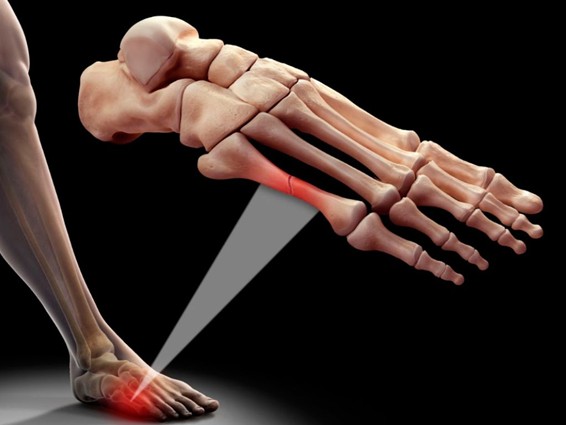

Las fracturas por estrés son pequeñas fisuras que ocurren en los huesos, normalmente en los metatarsianos. Estas fracturas pasan cuando en un hueso sano, con una resistencia normal, se les somete a fuerzas de repetición. Estas fracturas pueden aparecer en diferentes sitios del cuerpo, aunque habitualmente la fractura más frecuente por estrés es la de los huesos del pie, o fractura por fatiga.

Dentro de estos huesos, las zonas más comunes serían el cuello del segundo y tercer metatarso, debido a que es la zona que más carga recibe dentro del pie. Esta es una de las localizaciones más habituales, pero también se dan en muchas otras localizaciones, dependiente de la actividad que la origine.

Las fracturas por estrés más comunes en el pie afectan los metatarsianos o bien los del talón. Dependiendo de cuál sea el hueso en el que se produzca la fisura y de su ubicación en el pie, estas fracturas serán más o menos dolorosas.

- Fractura del segundo metatarsiano: es la más habitual, suele afectar a corredores, porque en la carrera este hueso está expuesto a una gran sobrecarga.

- Fractura del quinto metatarsiano: afecta al hueso que se encuentra en el lateral externo del pie y es común en deportistas que lo fuerzan cuando realizan desplazamientos lateralmente o por saltar, como jugadores de fútbol y baloncesto.